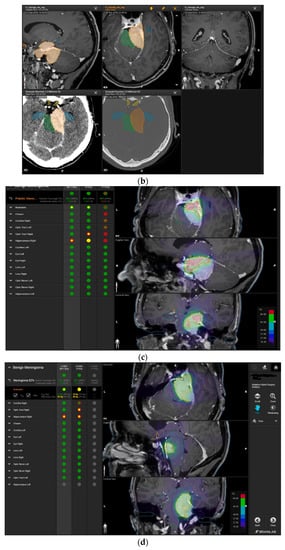

A 58-year-old female presented with progressive headache, difficulty swallowing, diplopia, hearing loss, and reduced face sensitivity on the right side (Figure 4). Elective craniotomy and AHSA-assisted tumor resection were performed. The patient underwent hypofractionated radiosurgery (5 × 5 Gy) of the residual meningioma one year after tumor resection.

Figure 4.

Second representative case of AHSA-supported tumor resection. (a) MRI imaging of petroclival meningioma (axial, coronal, sagittal). (b) Depiction of preoperative tumor volume (orange) and planned residual tumor volume (red). (c) AHSA summary table showing the stereotactic radiation constraints for the preoperatively planned residual tumor volume. With this plan, conventional fractionation and hypofractionation were feasible with effective tumor coverage.

—brainstem: mean dose is safe, while the max. dose is marginally safe;

—right optic tract: mean dose unsafe, max. dose is marginally safe;

—right hippocampus: marginally safe, and mean dose unsafe, max. dose is marginally safe. (d) First intraoperative structure update (ISU) with a residual tumor volume of 82% with the calculated dose constraints for conventional and hypofractionated radiotherapy. Single dose stereotactic radiosurgery was not feasible with this degree of remaining tumor. At this point, the dose constraints for conventional radiotherapy were:

—brainstem: mean dose is safe, max. dose is marginally safe;

—right hippocampus: mean dose unsafe, max. dose is marginally safe. Hypofractionated radiotherapy:

—brainstem: marginally safe;

—right cochlea: mean dose unsafe, max. dose safe;

—right hippocampus: mean dose unsafe, max. dose is marginally safe. (e) Second intraoperative ISU with residual tumor volume of 74% and calculated dose constraints for hypofractionated radiotherapy. Single dose stereotactic radiosurgery was still not considered feasible with this residual tumor volume. The dose constraints for organs at risk for conventional and hypofractionated radiotherapy were unchanged compared to the first ISU. (f) Third intraoperative ISU with residual tumor volume of 47% and calculated dose constraints for conventional, hypofractionated radiotherapy, and radiosurgery. The current dose constraints for organs at risk were the following for conventional radiation:

—right hippocampus: mean dose unsafe, max. dose is marginally safe. Hypofractionated radiation, which was unchanged for the first and second ISU:

—right hippocampus: mean dose unsafe, max. dose is marginally safe. For single fraction radiosurgery, the OAR dose constraints were available but considered to be unsafe.

—brainstem: mean dose unsafe, max. dose safe;

—chiasma: unsafe;

—right cochlea: unsafe;

—left optic tract: mean dose unsafe, max. dose safe;

—right optic tract: unsafe;

—right hippocampus: unsafe. (g) Overlay of preoperatively estimated and intraoperative effective residual tumor volume in AHSA. (h) Final intraoperative dose constraints after last ISU and data fusion with intraoperative CT. The dose constraints for OARs appeared to improve and were as follows for conventional and hypofractionated radiotherapy:

—brainstem: mean dose is safe, max. dose is marginally safe.

—brainstem: mean dose safe, max. dose unsafe;

—chiasm: mean dose unsafe, max. dose safe;

—right optic tract: mean dose unsafe, max. dose safe. (i) Comparison of pre- and 3 months postoperative MRI for stereotactic radiation planning. The residual tumor was finally treated with hypofractionated radiotherapy (5 × 5 Gy).